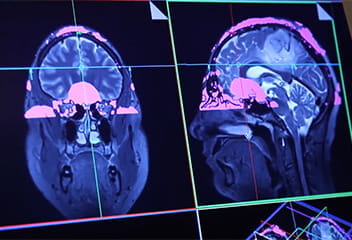

Head and brain scan in two views

IU School of Medicine has amassed an extensive array of imaging tools for neuroscience research, including multiple MRI and PET scanners, cyclotrons to produce radioactive trace elements, and the capacity to process images and store enormous data files.

These imaging tools provide 3D views of the brain, its structures, abnormalities, and protein compositions— tremendous tools that would be applied to bipolar disorder research.